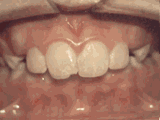

overbite

Overbite: Protruding front teeth

At age ten, patient had a big overbite with the top teeth protruding beyond the bottom. She had two phases of treatment. The first helped her jaws to grow more harmoniously; the second aligned her teeth and bite. At age thirteen, she was proudly displaying her new smile.